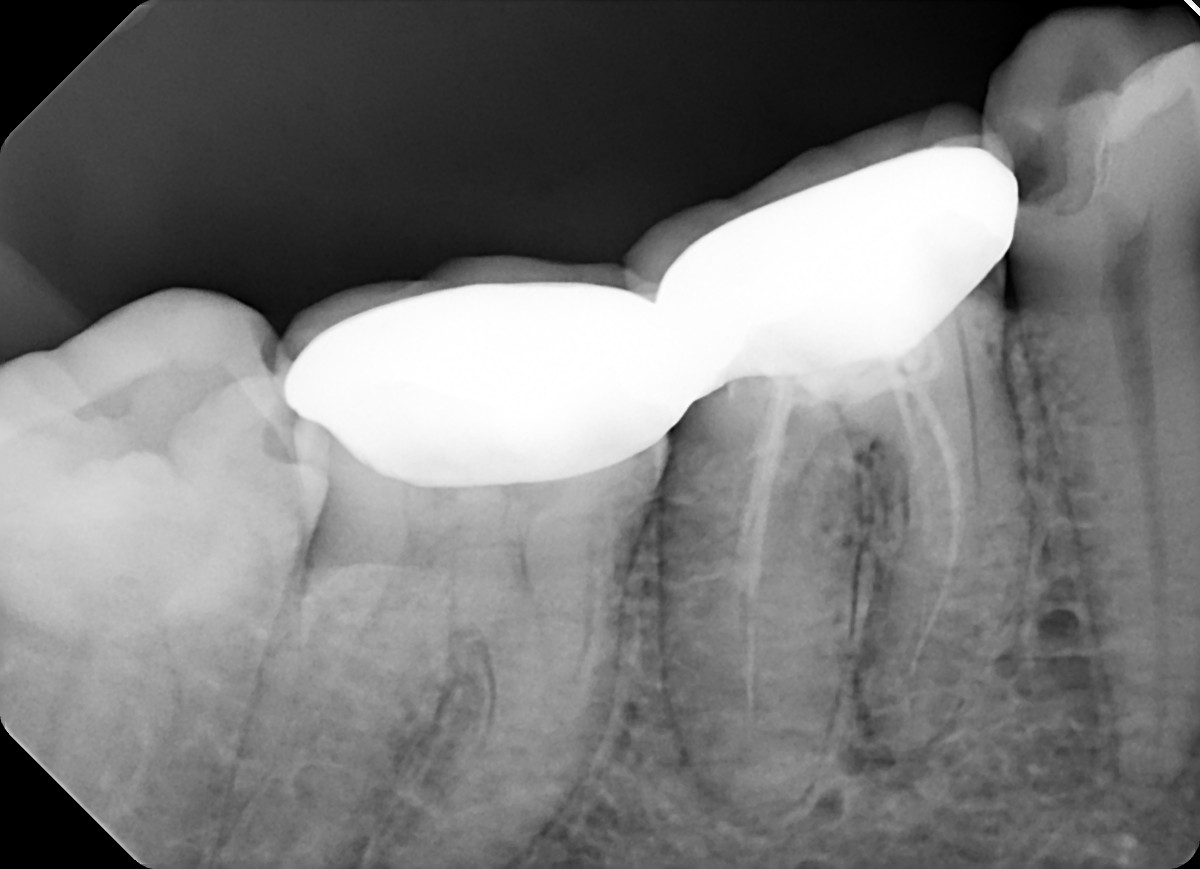

4. Evaluate the root canal treatment of tooth # 3.6?